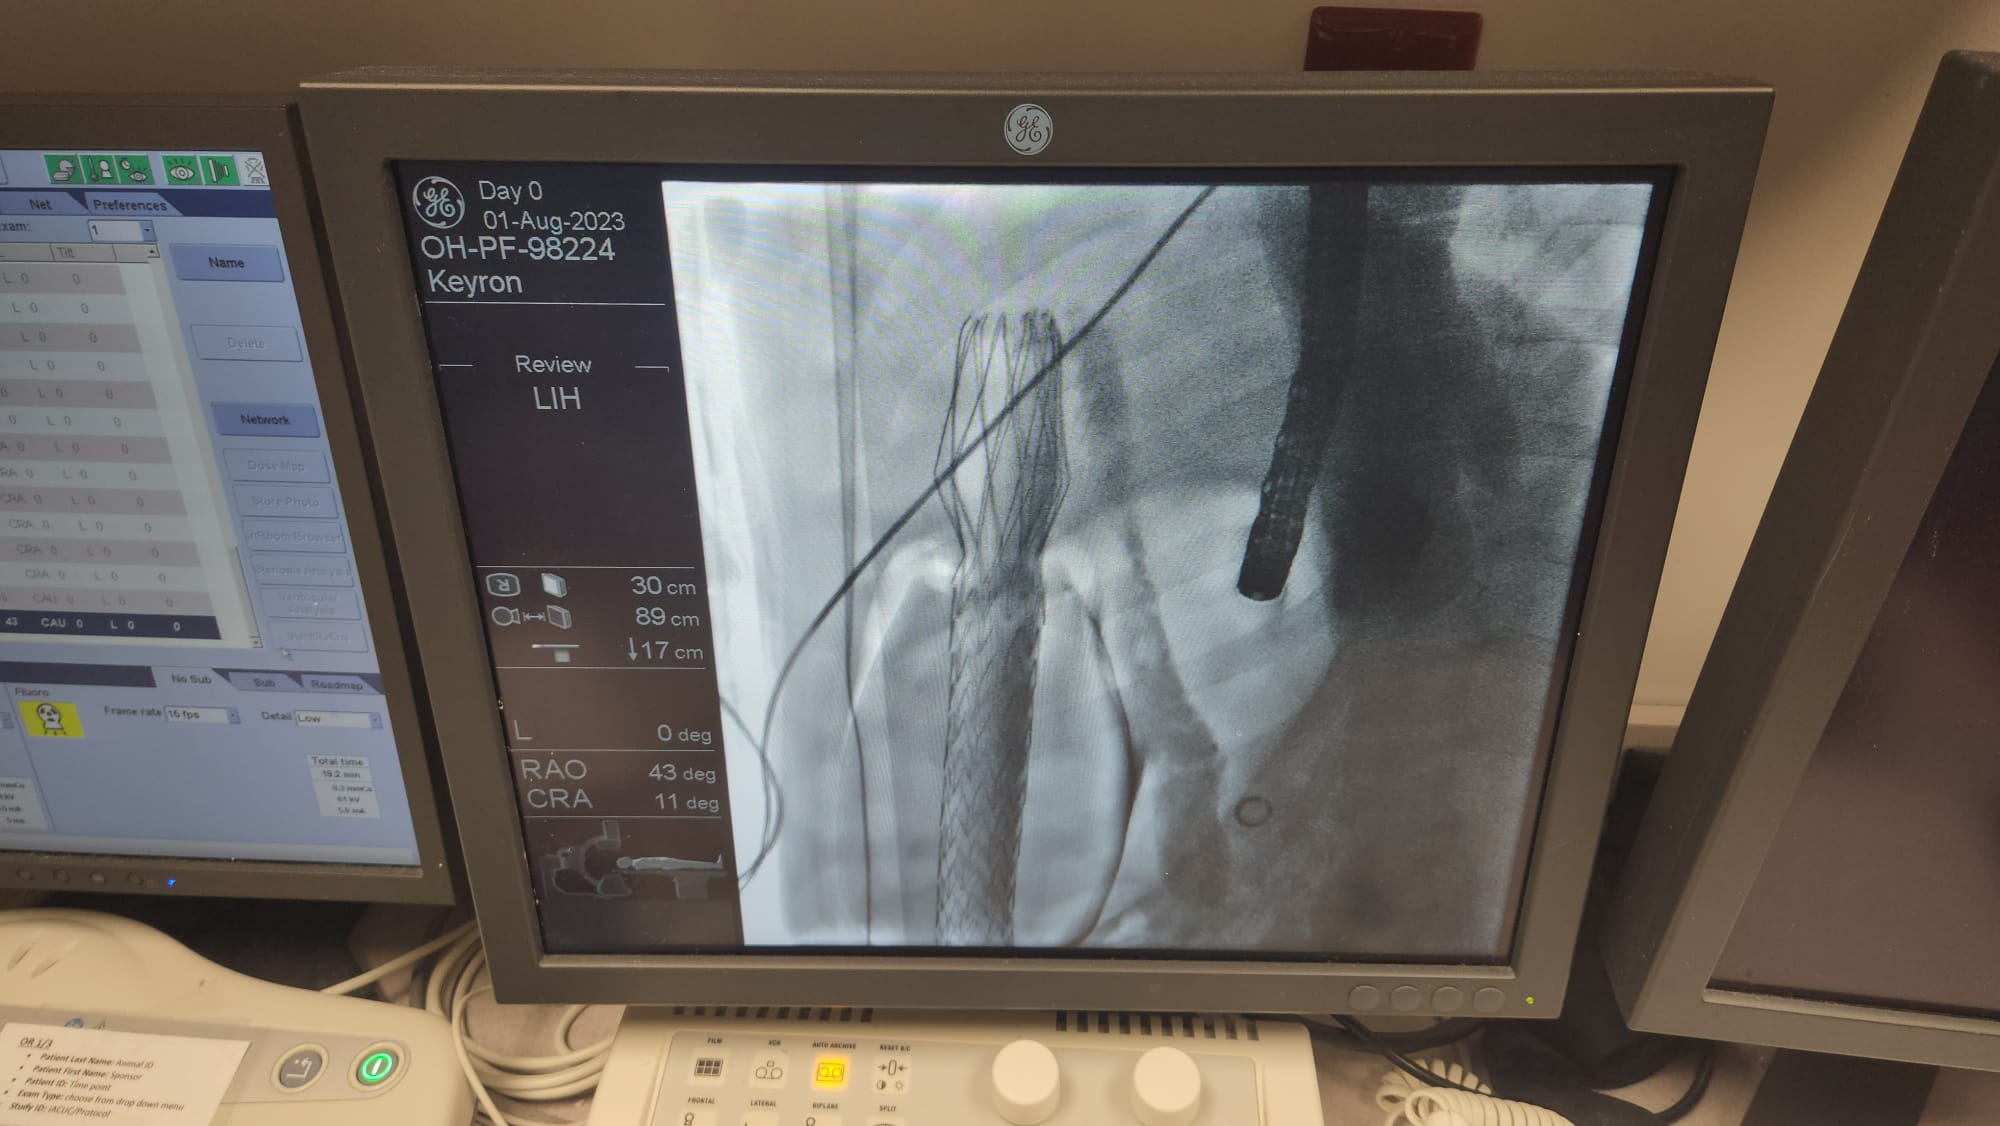

Our large animal data was published in Gut, the world’s leading journal in gastroenterology and hepatology, and the official journal of the British Society of Gastroenterology, with an exceptionally high impact factor of 25.8.

Pre-clinical studies have shown that the efficacy of ForePass ® may be unprecedented, and likely even better than Roux-en-Y Gastric Bypass surgery. Our long-term animal data shows (Δ from Baseline vs endoscopic controls):

Conclusion: ForePass ® reduced body weight, glycemia and insulin resistance, and liver fat deposition to the same level of gastric bypass surgery

We demonstrated a full reversal of diabetes and NASH, and weight loss, to levels not statistically different from gastric bypass surgery

ForePass ® is an extremely promising technology which may allow us to deliver the same benefits of metabolic surgery but without the complications from a surgical procedure

ForePass could allow many more people to access the efficacy that metabolic surgery is known for. Its elegant anchoring system could ensure the required safety that so many other devices in the space have not been able to achieve